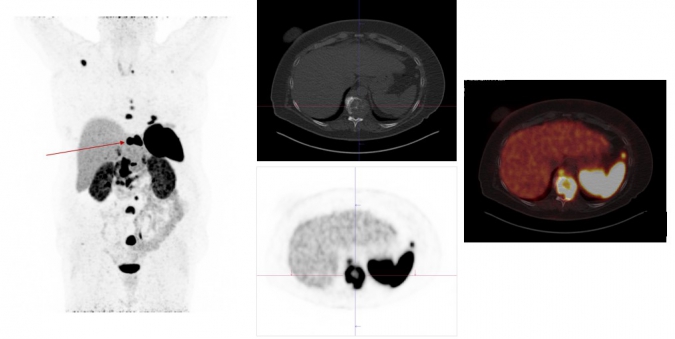

Exemplary case study on Ga-68-DOTANOC-PET/CT diagnostics: